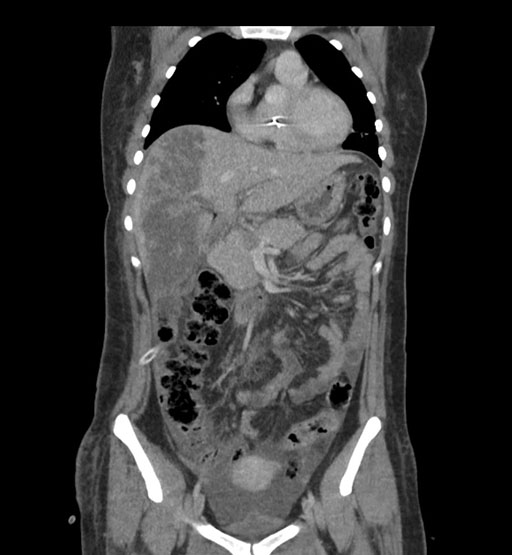

Imaging Analysis

Look through the patient's CT scan to identify any areas of concern for the necessary procedure.

Coronal Venous

Based on initial findings, which issue(s) would you be most concerned about?